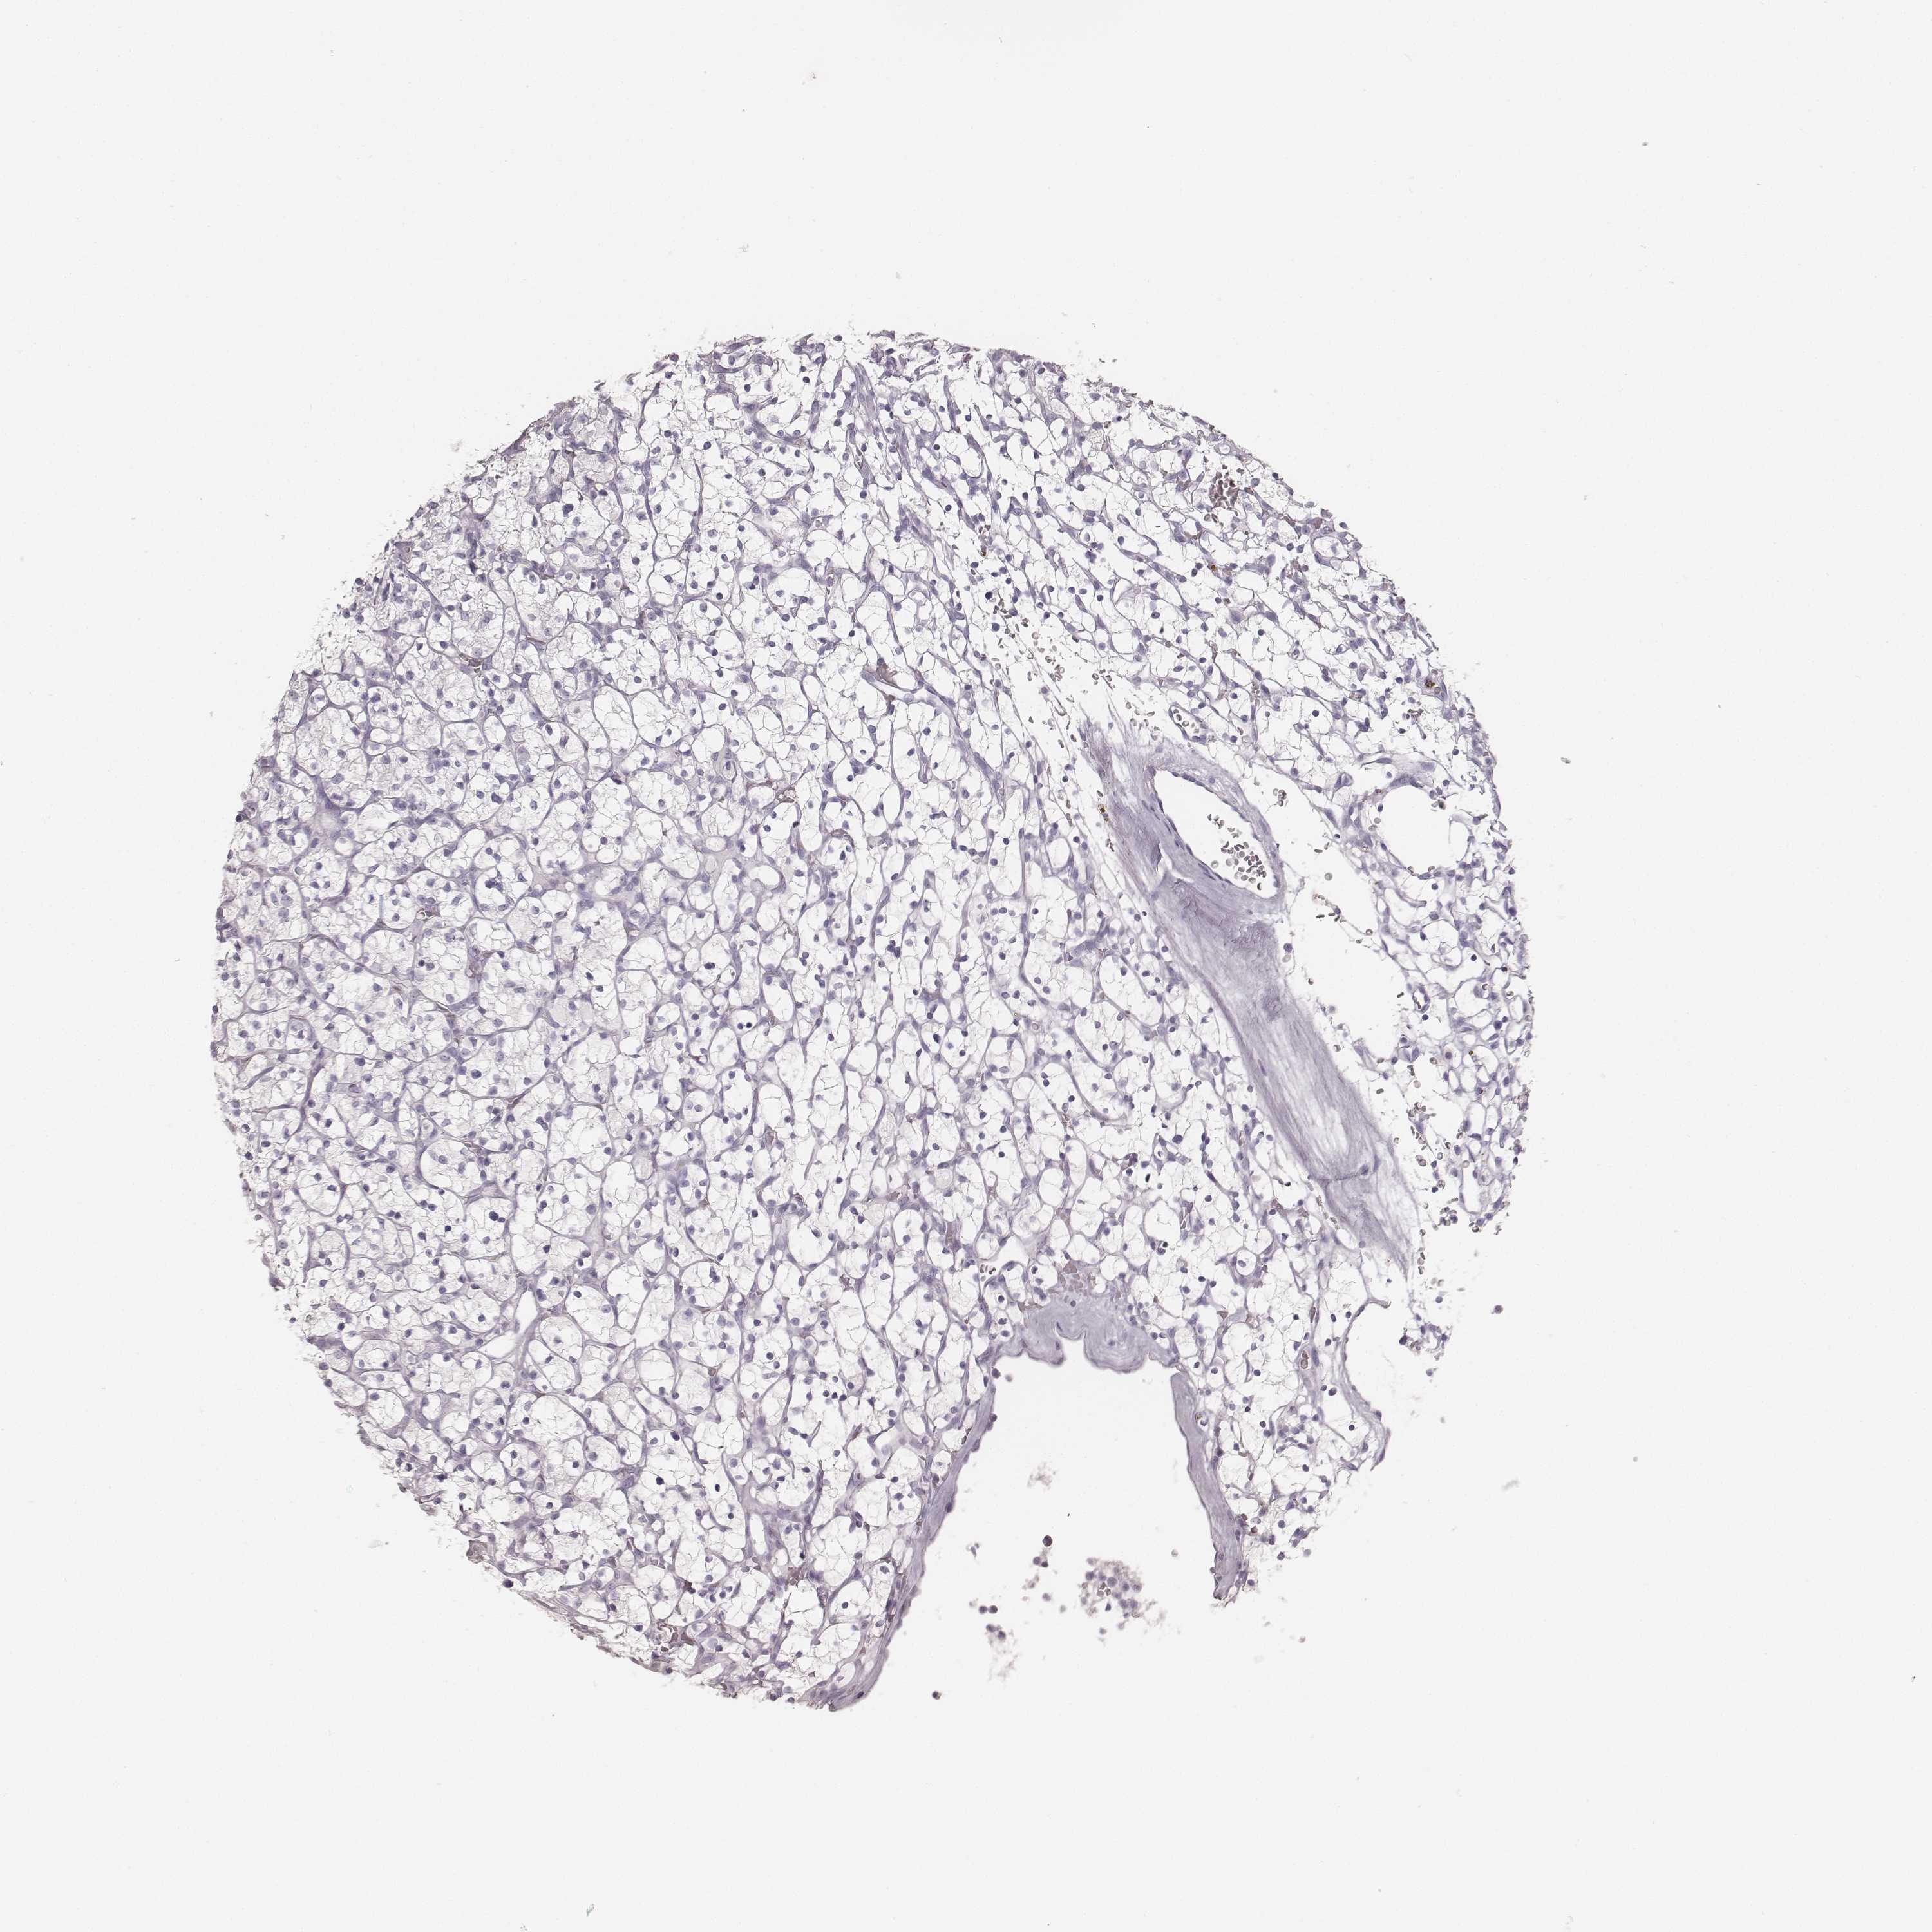

KICH TCGA KIRC TCGA KIRC VALIDATION KIRP TCGA PROTEIN RCC CPTAC PROTEIN EXPRESSION

KIDNEY RENAL CLEAR CELL CARCINOMA (TCGA) - Interactive survival scatter ploti

The Survival Scatter plot shows the clinical status (i.e. dead or alive) for all individuals in the patient cohort, based on the same data that underlies the corresponding Kaplan-Meier plots. Patients that are alive at last time for follow-up are shown in blue and patients who have died during the study are shown in red.

The x-axis shows the expression levels (FPKM) of the investigated gene in the tumor tissue at the time of diagnosis. The y-axis shows the follow-up time after diagnosis (years). Both axes are complimented with kernel density curves demonstrating the data density over the axes. The top density plot shows the expression levels (FPKM) distribution among dead (red) and alive patients (blue). The right density plot shows the data density of the survived years of dead patients with high and low expression levels respectively, stratified using the cutoff indicated by the vertical dashed line through the Survival Scatter plot. This cutoff is automatically defined based on the FPKM cutoff that minimizes the p-score. The cutoff can be changed by dragging the vertical line or by entering a cutoff value in the square labeled "Current cut-off".

Under the Survival Scatter plot the p-score landscape (black curve; left axis) is shown together with dead median separation (red curve; right axis). Dead median separation is the difference in median mRNA expression between patients who have died with high and low expression, respectively. It is calculated as follows: median FPKM expression of dead patients with high expression - median FPKM expression of dead patients with low expression. This is intended to aid the user in visually exploring custom cutoffs and the associated p-scores and dead median separation.

Individual patient data is displayed and can be filtered by clicking on one or more of the category buttons on the top of the page. Categories describing expression level and patient information include: high, low, alive, dead, female, male and tumor stages. The scale of the x-axis can be toggled between linear and log-scale by clicking on the "x log" button. Mouse-over function shows TCGA ID, patient information and mRNA expression (FPKM) for each patient.

& Survival analysisi

Kaplan-Meier plots summarize results from analysis of correlation between mRNA expression level and patient survival. Patients were divided based on level of expression into one of the two groups "low" (under cut off) or "high" (over cut off). X-axis shows time for survival (years) and y-axis shows the probability of survival, where 1.0 corresponds to 100 percent.

Survival analysis data not available.

TCGA RNA samplesi

RNA-seq data is reported as average FPKM (number Fragments Per Kilobase of exon per Million reads), generated by the The Cancer Genome Atlas (TCGA) .

Normal distribution across the dataset is visualized with box plots, shown as median and 25th and 75th percentiles. Points are displayed as outliers if they are above or below 1.5 times the interquartile range. FPKM values of the individual samples are presented next to the box plot.

Average pTPM 0.0

Number of samples 521